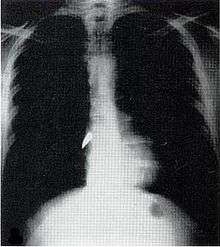

Most penetrating injuries are chest wounds and have a mortality rate (death rate) of under 10%.[11] Penetrating chest trauma can injure vital organs such as the heart and lungs and can interfere with breathing and circulation. Lung injuries that can be caused by penetrating trauma include pulmonary laceration (a cut or tear) pulmonary contusion (a bruise), hemothorax (an accumulation of blood in the chest cavity outside of the lung), pneumothorax (an accumulation of air in the chest cavity) and hemopneumothorax (accumulation of both blood and air). Sucking chest wounds and tension pneumothorax may result.

Penetrating trauma can also cause injuries to the heart and circulatory system. When the heart is punctured, it may bleed profusely into the chest cavity if the membrane around it (the pericardium) is significantly torn, or it may cause pericardial tamponade if the pericardium is not disrupted.[12] In pericardial tamponade, blood escapes from the heart but is trapped within the pericardium, so pressure builds up between the pericardium and the heart, compressing the latter and interfering with its pumping.[12] Fractures of the ribs commonly produce penetrating chest trauma when sharp bone ends pierce tissues.